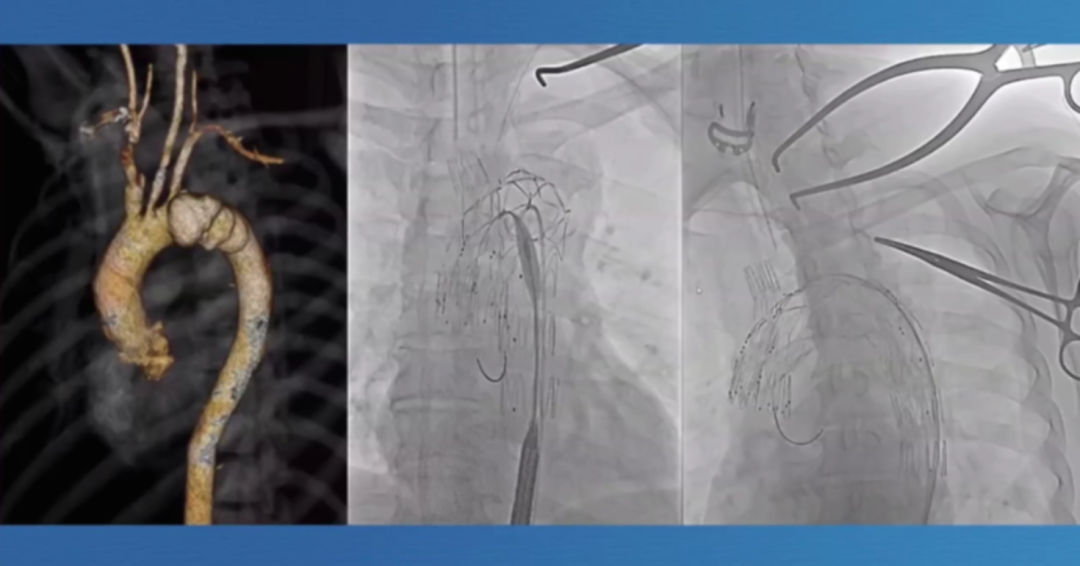

国际分支支新进展

Gore TAG支架于2022年底获FDA批准,采用单侧臂分支至锁骨下动脉的技术设计,30天结果表现出色,技术成功率达91.7%-97.4%,致残性中风3.6%,永久性截瘫1.2%。

Castor支架则专为B型夹层设计,结合中国患者特点优化,上市前研究提示手术成功率超95%,不过有50%患者撕裂延伸至左锁骨下动脉。上市后研究提示手术成功率达98.15%,分支血管通畅率为100%,再次干预率为0,且住院死亡率、夹层破裂率均为0,相比上市前有明显提升。同时,上市后研究里,术前CTA测量显示撕裂向左侧锁骨下动脉逆行占比为0%,这也从侧面反映出病情特征利于治疗开展。

Castor上市后研究还明确了其解剖适配性:65.8%患者支架着陆于2区(Zone2),52.2%为III型主动脉弓,46.8%患者夹层破口逆行至左锁骨下动脉(LSA),提示其对复杂解剖的适应能力。

第二代分支支架在设计上进一步优化,Cook LSA分支支架(Gen2)采用三角形凹槽设计,要求左颈总动脉与左锁骨下动脉间距25mm,分支开口与织物端距离60mm,其预装导管系统使分支接入更简便,为临床操作提供了便利。